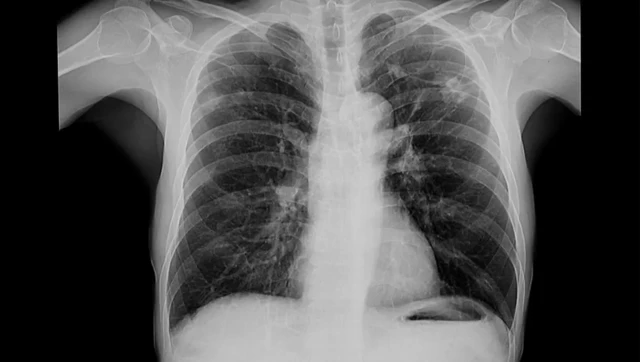

కేంద్ర ఆరోగ్య శాఖ సమాచారం ప్రకారం.. ఊపిరితిత్తుల కణాల్లో ఇన్ఫ్లమేషన్ను న్యుమోనియాగా పిలుస్తారు. ఊపిరితిత్తుల్లో చిన్నచిన్న గాలి గదులు ఉంటాయి. వీటినే ‘‘అల్వెయోలై’’గా పిలుస్తారు. వీటిల్లోకి బ్యాక్టీరియా చేరడంతో న్యుమోనియా సోకుతుంది.

బ్యాక్టీరియా ద్వారా న్యుమోనియా సోకినప్పుడు.. అల్వెయోలైలో నీరు, చీము పేరుకుంటాయి. వీటి వల్ల అల్వెయోలై పనితీరు మందగిస్తుంది. ఫలితంగా శ్వాస తీసుకోవడం కష్టం అవుతుంది. ఫలితంగా రక్తంలో కలిసే ఆక్సిజన్ పరమాణువుల సంఖ్య తగ్గిపోతుంది.

న్యుమోనియాను వెంటనే గుర్తించి, చికిత్స తీసుకోవడం చాలా ముఖ్యమని నిపుణులు చెబుతున్నారు. ‘‘అన్ని రకాల న్యుమోనియాలు ప్రాణాంతకం కాదు. అయితే, అసలు న్యుమోనియా ఎలాంటిదో ముందుగా పరీక్షల సాయంతో తెలుసుకోవాలి. ఇక్కడ చికిత్స అనేది చాలా ముఖ్యం’’అని పల్మనాలజిస్టు డాక్టర్ సలీల్ బింద్రే చెప్పారు.